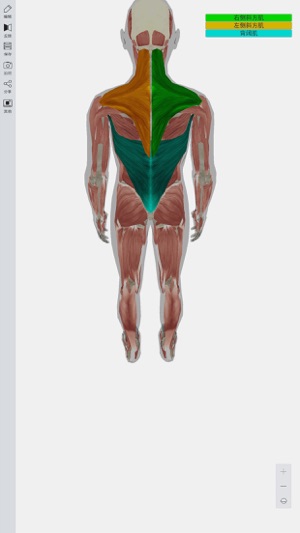

3D人体模型提供全三维数字人体模型,超过4000多个人体解剖结构,完整全面的解剖学数据,涵盖人体各个解剖系统,如神经,运动,呼吸,心血管,泌尿等系统,并配有文字注释,触发点等信息。

此APP功能强大,是广受欢迎的医学软件之一。其主要包括12个系统:

循环系统,消化系统,内分泌系统,皮肤系统,淋巴系统,肌肉系统,神经系统,生殖系统,泌尿系统,呼吸系统,骨骼系统和骨连接系统。

真正的3D特效,能360度任意角度查看,分层查看,进行相关组织或解剖结构隐藏,显示,完全再现人体解剖全过程。